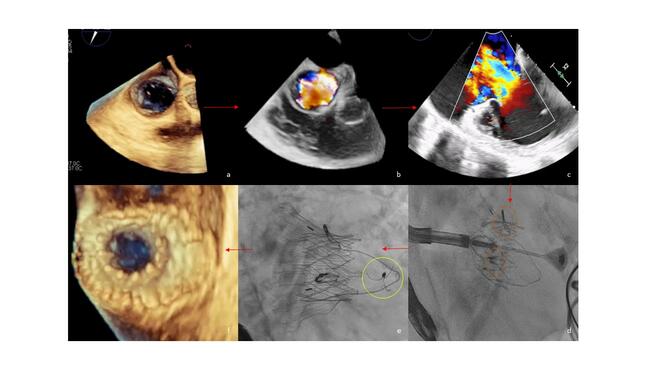

TTVR with a LuX-Valve Plus has been described elsewhere.1 Briefly, under general anesthesia with fluoroscopic and transesophageal echocardiogram (TEE) guidance, a 30/55 LuX-Valve Plus was successfully deployed across the native tricuspid annulus via the right jugular vein (33F delivery system). After adjusting the delivery system to be in the center and perpendicular to the tricuspid annulus, the “rabbit-ears” graspers (Figure D) were released and the anchor tongue was fired onto the ventricular septum (Figure E), stabilizing the platform. The delivery system was then removed.

Post-deployment imaging confirmed a good valve position, elimination of the TR, and a preserved RV function (Figure F) (Videos 5 and 6). Repeat TTE before discharge showed a well-seated bioprosthesis with no residual TR and improved RV dimensions. The patient was alive and doing well 3 months post-TTVR.

Figure. (A) Transesophageal echocardiogram (TEE) 3-dimensional (3D) image at 65o of the tricuspid valve annulus (area 15.2 cm2). (B) TEE image with 3D color Doppler showing the massive tricuspid regurgitation (TR). (C) TEE image at 0o depicting the massive TR. (D) The 2 ‘rabbit-ears’ graspers are seen clipping the leaflets (orange circles). (E) The LuX-Valve Plus (Jenscare Scientific Co. Ltd.) is released and the anchor has attached in the septum (yellow circle). (F) TEE 3D image at 70o showing the well-opposed prosthetic valve.